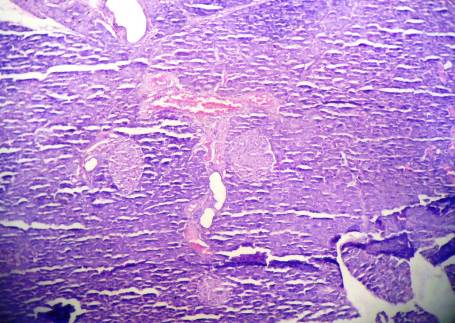

Group II: Toxic Control (Alloxan monohydrate)

Fig. 9: The numbers of islets cells were severely decreased, islets cells were severely swelled